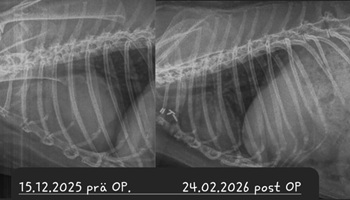

• Röntgen

Ein Kaninchen mit Atembeschwerden oder den beschriebenen Augenveränderungen sollte zunächst geröngt werden. Hierdurch lassen sich Verschattungen im Brustkorb schnell und einfach erkennen und es muss anschließend nur noch ermittelt werden, ob es sich dabei um einen Tumor oder eine (reine) Herzerkrankung handelt. Letztere kann zu einem vergrößerten Herzen oder einem Erguss führen, was per Röntgendiagnostik nicht immer von einem Tumor zu unterscheiden ist.

Operation

Bei einer Thymom- oder Lymphom-OP handelt sich um einen schwerwiegenden Eingriff, bei dem der Brustkorb des Patienten eröffnet wird und der Tumor möglichst vollständig entfernt werden muss, ohne dabei das benachbarte Herz zu schädigen. Die OP wird nur von wenigen Chirurgen angeboten. Ein Spezialist, der regelmäßig auch Patienten aus Deutschland operiert, ist Dr. Florent Modesto in Brüssel.

Sofern davon auszugehen ist, dass das Kaninchen den Eingriff übersteht und der Tumor sich vollständig entfernen lässt, ist die OP zwar die kostspieligste, aber vermutlich auch die Option mit der besten Prognose

Leider ist trotz allem damit zu rechnen, dass Zellreste des Tumors zurückbleiben und nach einiger Zeit nachwachsen. Je nach Tumor-Art ist dies allerdings mitunter erst nach 3-5 Jahren der Fall - womit das Kaninchen sehr viel Lebenszeit gewonnen hat; hinzu kommt die verbesserte Lebensqualität, nachdem die Masse aus dem Brustkorb entfernt wurde und langfristig auch keine Medikamente gegeben werden müssen.

Nach der chirurgischen Entfernung des Tumors bleibt der Patient stationär am Schmerzmittel-Dauertropf, bis er stabil bei gutem Allgemeinbefinden ist.

Um eine komplikationslose Heilung der Nähte und des Brustbeins zu gewährleisten, muss das Kaninchen in den ersten 4 Wochen nach der OP in einem kleinen Krankenbereich (Zimmerkäfig oder kleines Gehege) untergebracht werden, da es keinesfalls rennen, springen oder übermäßig hoppeln darf.